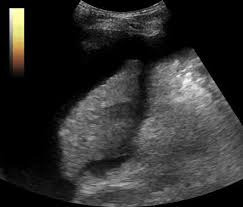

복부 초음파는 초음파(ultrasound)를 이용해 복부 내 장기들의 상태를 확인하는 비침습적 검사 방법입니다. 방사선을 사용하지 않아 인체에 해롭지 않고, 고통 없이 실시간으로 복부 장기들을 관찰할 수 있다는 점에서 가장 기본적이면서도 효과적인 진단도구로 평가받습니다.

초음파 탐촉자(Probe)에서 발생한 고주파 음파가 인체 내부 장기에 부딪혀 반사되며, 복부 초음파로 알 수 있는 것은 바로 이 반사파를 영상화해 간, 담낭, 췌장, 비장, 신장(콩팥), 방광, 대동맥, 림프절 등의 상태를 분석하게 됩니다.

신장(콩팥) 질환

- 신장 결석

- 수신증

- 신장 낭종

- 신세포암